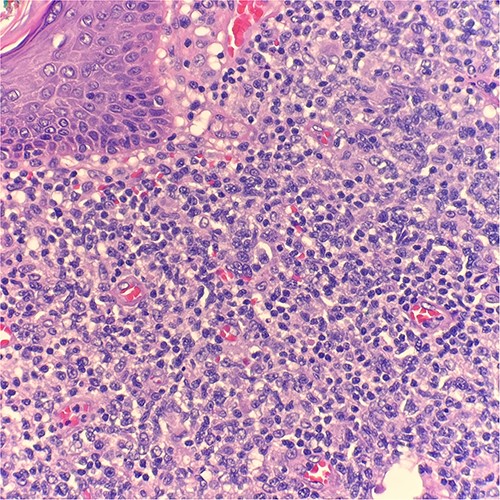

Microscopic examination reveals skin and subcutaneous tissue with atypical nodular nested lymphoid infiltrate in the dermis. The infiltrate is composed of intermediated cells with irregular nuclei, dispersed chromatin and variably conspicuous nucleoli mixed with large cells (Fig. 1). The atypical cells are positive for CD20 (Fig. 2) and BCL6 (Fig. 3). The morphological findings along with the skin location are consistent with primary cutaneous follicle center lymphoma (PCFCL).

Microscopic examination reveals skin and subcutaneous tissue with atypical nodular nested lymphoid infiltrate in the dermis. H&E 40×.